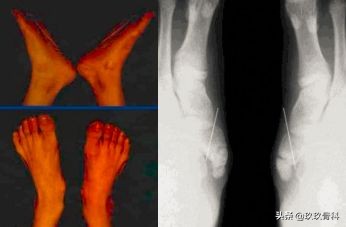

运动员的副舟骨损伤▲▲▲

解剖:圆形,与舟状骨体无接触面,像髌骨一样长于胫后肌腱上,其底面为关节面,一般不产生症状。

长形,舟状骨的颈较长,副舟骨与之接触,为圆形或三角形,此型很易受伤引起症状。副舟骨与舟状骨之间的连接组织为玻璃软骨,纤维软骨。

受伤原因及损伤机制:外伤所致,少数与劳损有关,多伴有平足。

早期多因急性扭伤引起,常被外侧副韧带损伤的症状所掩盖,恢复运动后,因内侧疼痛而被发现。主要症状表现为蹬地、跑跳时疼痛加重。

临床体征:副舟骨部突出,局部压痛,足内收抗阻痛。